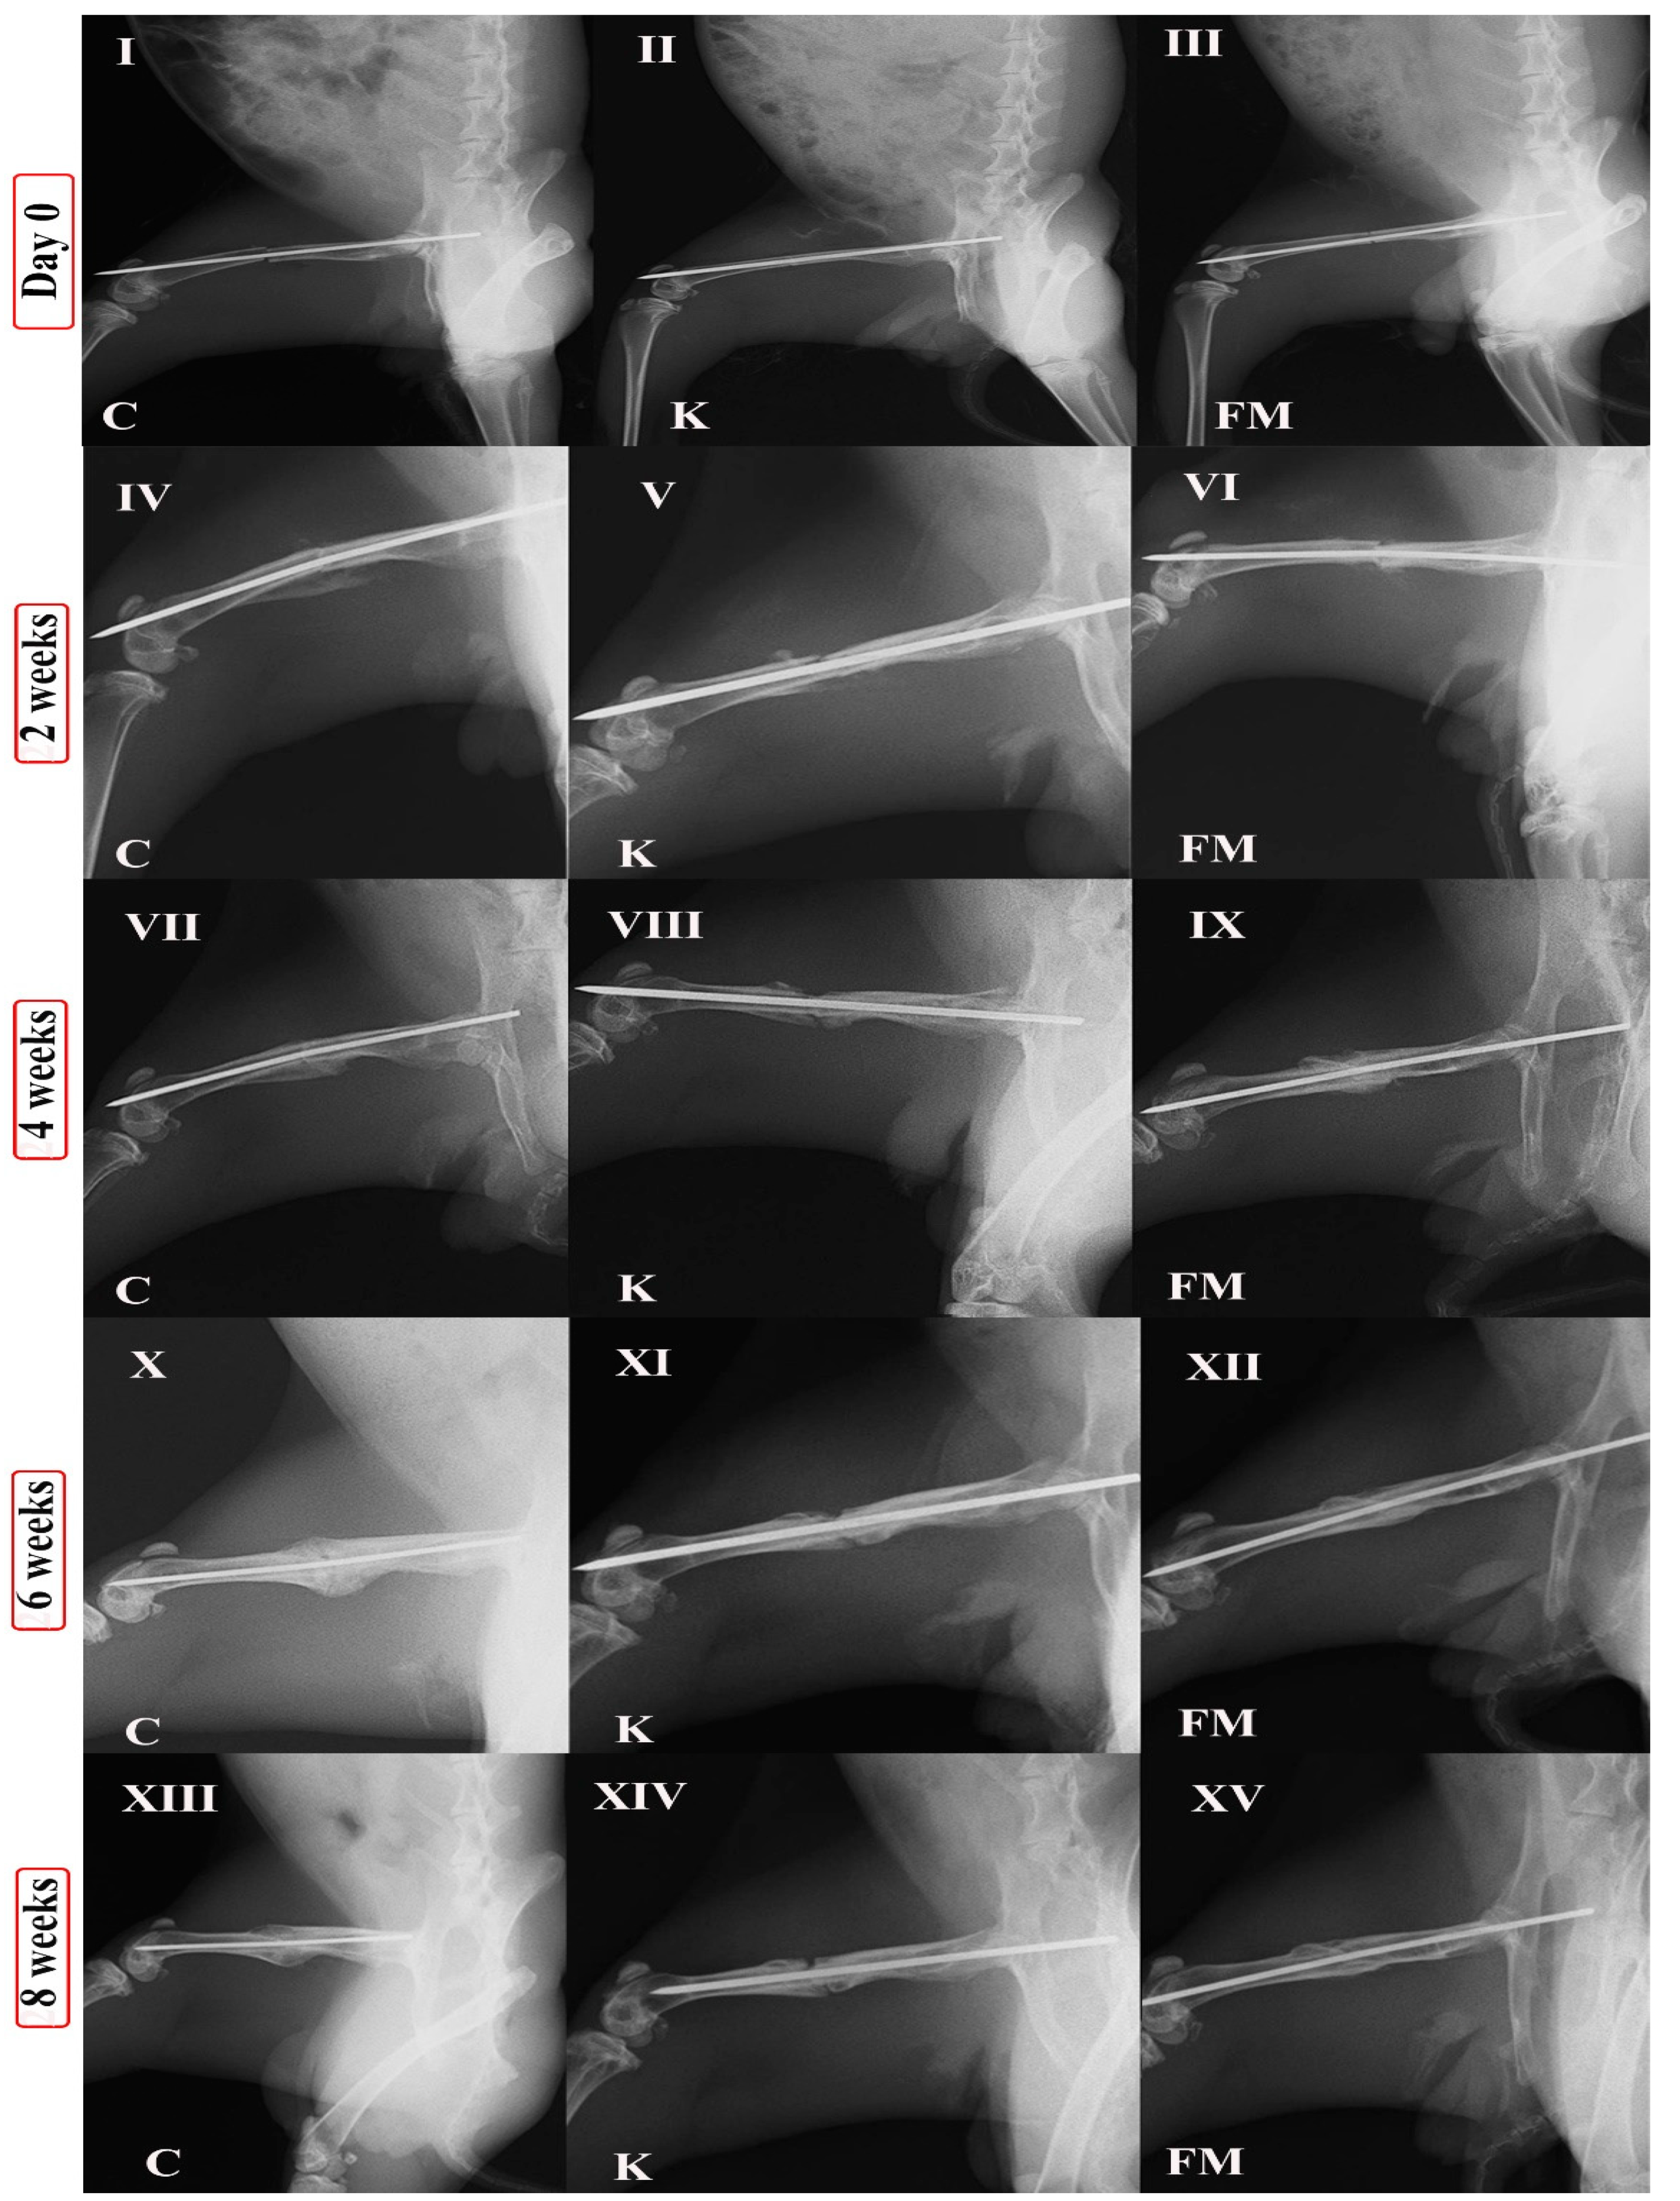

3.1. Radiographic Findings

| Timeline | Callus Formation | Bone Union | Bone Remodeling | p Value | ||||||

|---|---|---|---|---|---|---|---|---|---|---|

| Control | Ketoprofen | FM | Control | Ketoprofen | FM | Control | Ketoprofen | FM | ||

| 2 weeks | 2.5 ± 0.54 | 2 ± 0.84 | 3.14 ± 0.51 | 1.66 ± 0.51 | 0.83 ± 0.40 | 2.40 ± 0.40 | - | - | - | p < 0.05 |

| 4 weeks | 2.67 ± 0.52 | 1.66 ± 0.82 | 3.13 ± 0.51 | 1.83 ± 0.75 | 1.17 ± 0.75 | 2.42 ± 0.41 | - | - | - | p < 0.05 |

| 6 weeks | 3.17 ± 0.75 | 1.83 ± 0.75 | 2.29 ± 0.52 | 2.33 ± 0.52 | 1.17 ± 0.75 | 2.46 ± 0.40 | 0.33 ± 0.52 | 0 ± 0 | 1.33 ± 0.51 | p < 0.05 |

| 8 weeks | 2.67 ± 0.52 | 0.33 ± 0.52 | 0.59 ± 0.52 | 2.66 ± 0.52 | 0.33 ± 0.52 | 2.75 ± 0.41 | 1.33 ± 0.52 | 0 ± 0 | 2.33 ± 0.41 | p < 0.05 |